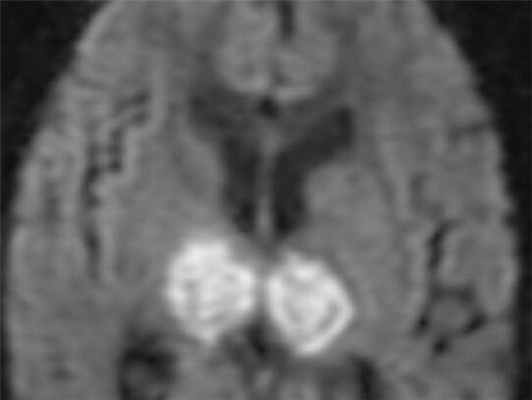

МРТ головного мозга. Аксиальная МРТ типа ДВИ. Двухсторонний венозный инфаркт зрительных бугров.